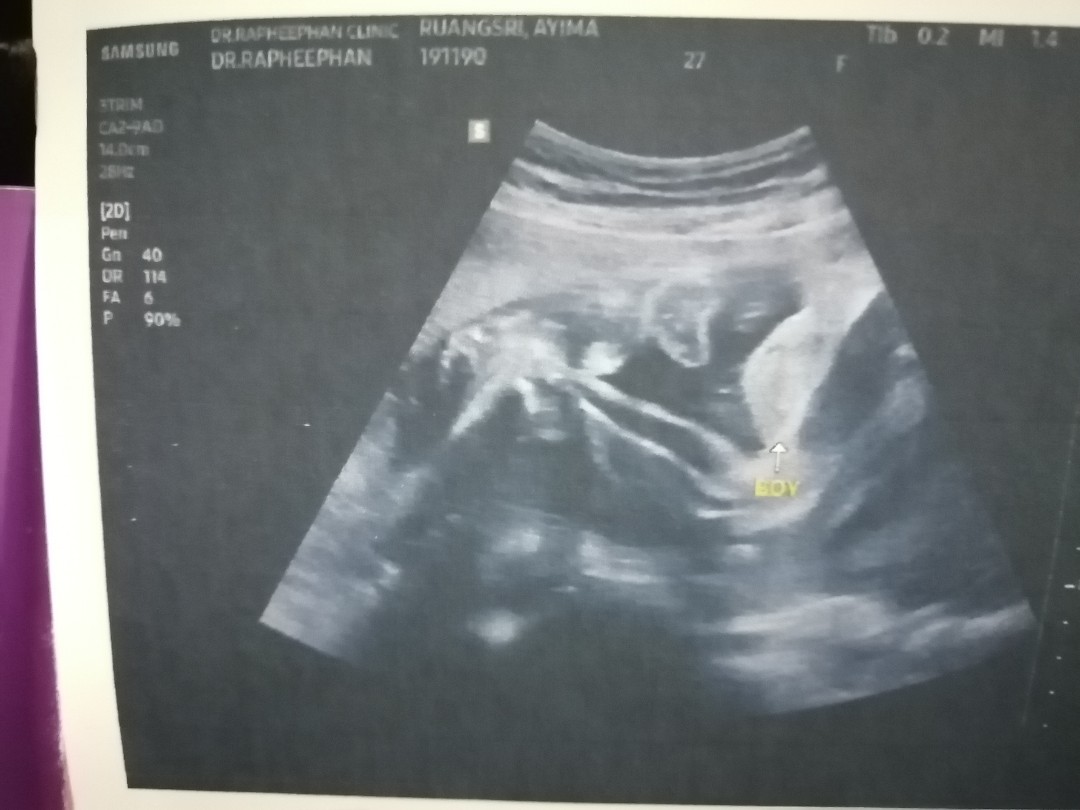

ชายค่ะ